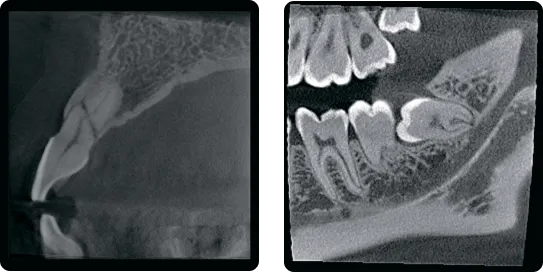

Сверхвысокое разрешение

Когда вам нужна очень точная детализация…

До 70 мкм режим сканирования для эндодонтии.

КТ-изображение с высоким разрешением в определённой области.